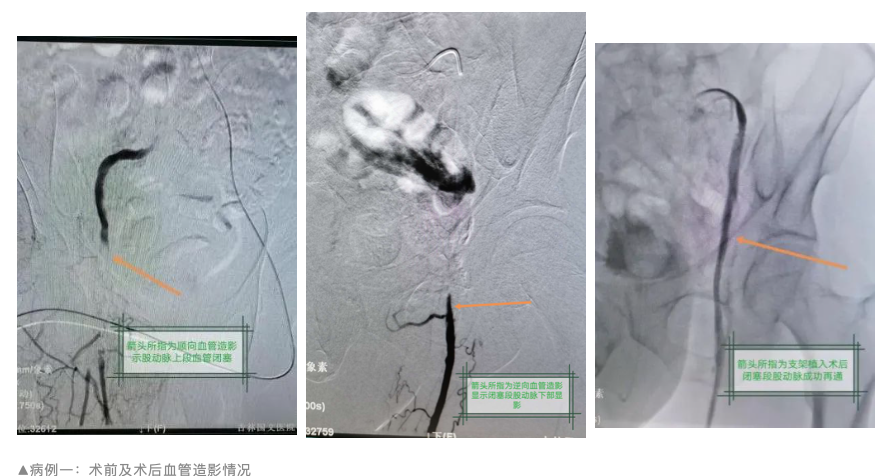

近日,吉林國(guó)文醫(yī)院介入治療科收治兩例因下肢皮溫發(fā)涼、行走時(shí)出現(xiàn)疼痛而前來就診的患者,其中一名患者左足踇趾已出現(xiàn)青紫樣改變。入院后給予行下肢動(dòng)脈CTA檢查后顯示,一例患者為左側(cè)髂外動(dòng)脈重度狹窄接近閉塞,一例患者為右側(cè)股動(dòng)脈上段閉塞,均考慮診斷為動(dòng)脈硬化閉塞癥。

4月10日在侯傳偉主任的帶領(lǐng)下,成功為兩名動(dòng)脈硬化閉塞癥患者實(shí)施了血管腔內(nèi)介入治療,其中還為一名患者成功實(shí)施了正向+逆向“對(duì)吻”技術(shù)。據(jù)了解,該項(xiàng)技術(shù)在吉林省內(nèi)處于領(lǐng)先水平。

術(shù)中通過正向?qū)Ыz技術(shù)反復(fù)嘗試進(jìn)入右側(cè)股動(dòng)脈側(cè)支,均無法通過閉塞段動(dòng)脈。此時(shí),侯傳偉主任仔細(xì)查看了影像情況,當(dāng)即決定采用逆行導(dǎo)絲技術(shù)完成經(jīng)皮血管腔內(nèi)介入治療。相對(duì)于正向?qū)Ыz技術(shù),逆向?qū)Ыz技術(shù)難度更大、風(fēng)險(xiǎn)更高,要求術(shù)者非常熟悉介入治療的各種技術(shù)操作手段。

由于患者右側(cè)股動(dòng)脈上段閉塞,下肢血流減少,右側(cè)腘動(dòng)脈穿刺難度較大,后在麻醉科劉桂穎主任協(xié)助下成功完成穿刺。隨后,侯傳偉主任憑借多年來的介入經(jīng)驗(yàn)和沉穩(wěn)操作,成功將導(dǎo)絲通過閉塞段股動(dòng)脈,最終使正向、逆向交匯。通道開通后,球囊擴(kuò)張及支架植入也順勢(shì)輕松完成。

術(shù)后,兩名患者皮膚溫度明顯改善,可觸及足背動(dòng)脈搏動(dòng),行走時(shí)未再出現(xiàn)下肢疼痛現(xiàn)象。